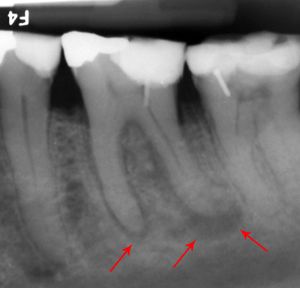

근관 치료의 또 다른 흔한 합병증은 근관 전체를 완전히 깨끗하게 청소하고 근관 충전재(보통 거타퍼차)로 채우지 못했을 때 발생한다. 반면에, 근관 충전재가 치근단에서 밀려나와 다른 합병증을 유발할 수도 있다. 위 그림의 엑스레이는 잘못된 근관 치료를 받은 인접한 두 개의 치아를 보여준다. 근관 충전재(3, 4 및 10)는 치아 뿌리(5, 6 및 11) 끝까지 확장되지 않는다. 치아 뿌리 하단의 어두운 원(7 및 8)은 주변 뼈의 감염을 나타낸다. 권장되는 치료법은 근관 치료를 다시 하거나 치아를 발치하고 임플란트를 식립하는 것이다. 불량한 품질의 충전재 또는 밀봉재도 근관 치료 실패의 원인이 될 수 있다.[46]

근관 치료를 받은 치아는 치과의사가 치아 내 모든 근관을 찾아서 세척하고 충전하지 못하는 경우와 같이 치유에 실패할 수 있다. 상악 어금니의 경우, 치아에 3개가 아닌 4개의 근관이 있을 확률이 50% 이상이지만, 종종 "근심 협측 2"라고 불리는 네 번째 근관은 보기가 매우 어렵고, 이를 보기 위해서는 특수 기구와 확대경이 필요한 경우가 많다(가장 흔하게 첫 번째 상악 어금니에서 발견된다. 연구에 따르면 이러한 치아의 평균 76%에서 최대 96%가 MB2 근관을 가지고 있다). 이 감염된 근관은 지속적인 감염이나 치아의 "악화"를 유발할 수 있다.